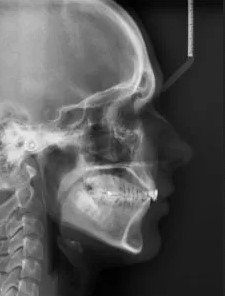

-zdjęcia cefalometryczne,